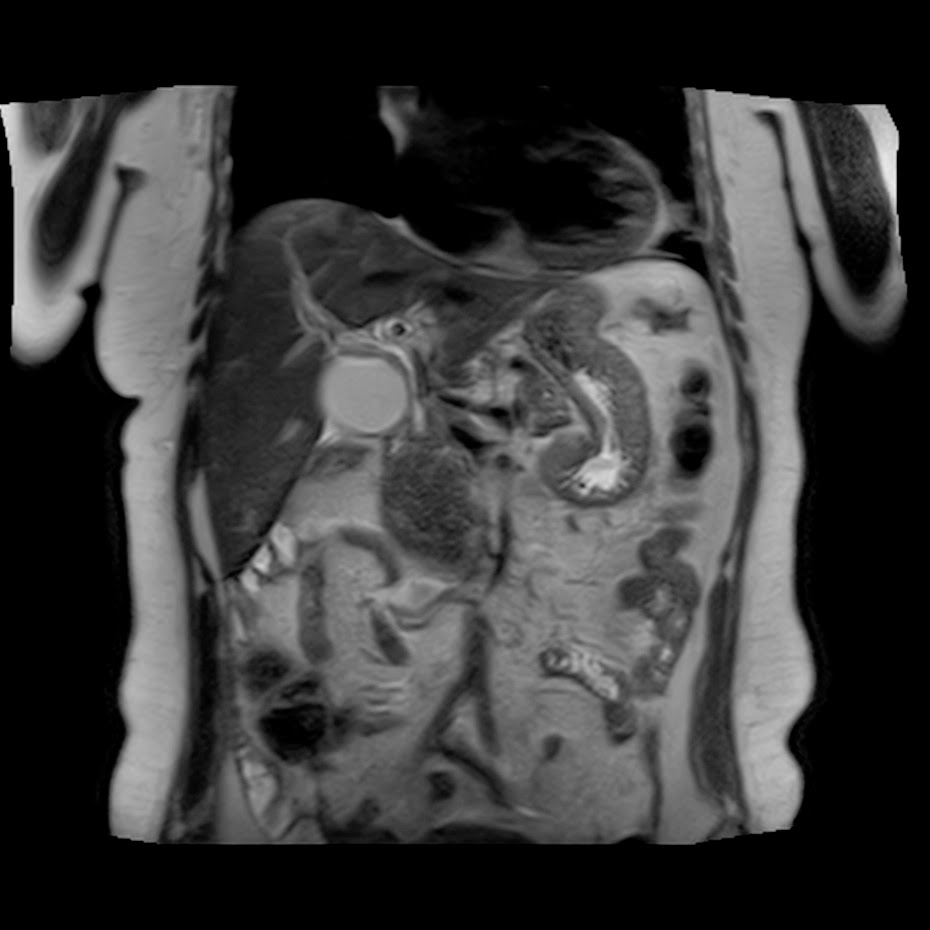

Caso interesante #5

Paciente con dolor en hipocondrio derecho.